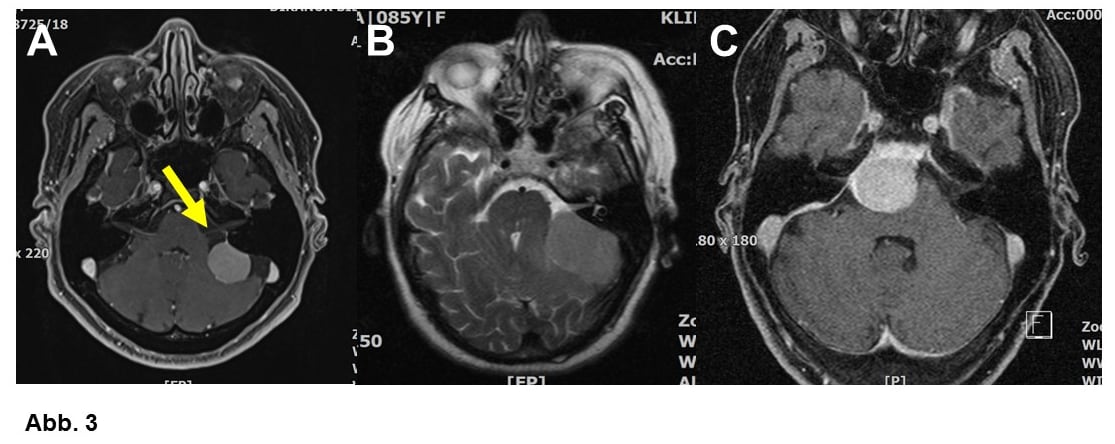

Von großer klinischer Bedeutung ist die Einteilung nach Lokalisation. Am häufigsten wachsen Meningeome ausgehend von der Hirnhaut über den Hemisphären (= Hirnhälften, Konvexitätsmeningeome, Abb. 1A-C) oder im Bereich einer bindegewebigen Sichel zwischen den Hemisphären (Falxmeningeom, Abb. 1C und D). Sogenannte Schädelbasismeningeome (Abb. 2, 3 und 4C) sind wegen ihrer Lage häufig schwieriger zu operieren als Konvexitäts- und Falxmeningeome. Meningeome können nicht nur ausgedehnt in den Hirnhäuten, sondern auch im Knochen (Abb. 4A und B) oder sogar vom Knochen ausgehend in die umgebenden Weichteile einwachsen (Abb. 4C). Meningeome im Bereich der Wirbelsäule (Abb. 5) sind seltener als im Kopf, sind aber umgekehrt häufige Tumoren im Rückenmarkskanal, wo sonst Tumoren eher selten sind. Bei bis zu 20% der Patienten liegen mehrere Meningeome vor (Abb. 1C).

Manche Meningeome werden im Anschluss an einem Krampfanfall diagnostiziert (Abb. 1B), kleine Meningeome sind ein häufiger Zufallsbefund (Abb. 1D), wenn aus ganz anderen Gründen ein CCT (Computertomogramm) oder MRT (Magnetresonanztomogramm) angefertigt worden ist. Große Tumoren können auch durch neurologische Symptome wie Sprachstörung, Lähmungen (Abb. 3C), Sehstörungen oder sogar Persönlichkeitsveränderungen auffallen (Abb. 1B). Bei entsprechender Lage kann ein Meningeom auch einmal den Hirnwasserabfluss stören und zu einem Wasserkopf (Hydrocephalus) führen. Kopfschmerzen sind häufig, selten aber durch den Tumor verursacht.

A. Schädelbasismeningeom (65-jährige Frau) im Bereich von Kleinhirn und Hirnstamm. Der Tumor hat noch reichlich Abstand vom Hör- und Gesichtsnerven (Pfeil).

B. Ähnliche Tumorlage, größerer Tumor, ältere Patientin (85 Jahre), entsprechend schwierigere Operation.

C. 54-jährige Patientin. Der Tumor drückte auf den Hirnstamm, die Patientin hatte eine leichte Lähmung. Die Operation war in diesem Fall wegen der großen Nähe zu wichtigen Blutgefäßen und Nerven besonders schwierig.